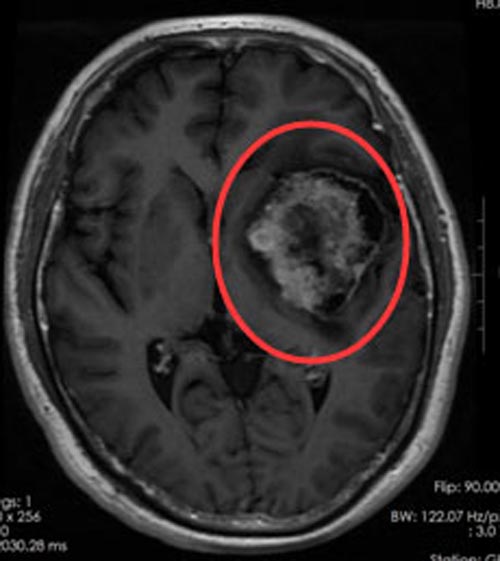

进一步检查发现:左额颞岛叶及基底节区块状占位性病变,病灶范围约7.2cm×4.7cm×5.4cm,左侧脑室受压变窄,中线结构稍右偏,周围脑组织水肿明显,有手术指征。家属同意手术治疗。

肿瘤位于功能区的语言中枢和运动中枢,与周围组织分界不清,既要最大限度地全切肿瘤,降低复发率,又要保护患者的语言及运动功能,这成为该手术的重中之重。由鲁明副院长主刀在全麻下行“左额颞岛叶及基底节区占位切除术”,术程顺利。术后,徐先生恢复满意,说话流利了许多,左侧肢体活动好,右侧肢体乏力也得到明显的改善。术后病理:非典型脑膜瘤,WHOⅡ级。